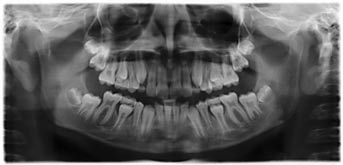

- Röntgenübersichtsaufnahme aller Zähne.

Sind alle Zähne angelegt?? Liegen Zähne quer? Wo fehlt Platz?